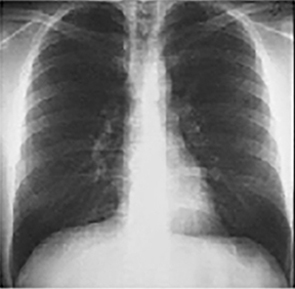

PA and Lateral

Click on the xrays to enlarge them.

Choose the best interpretation of the chest X rays in our patient:

Left ventricular enlargementand a dilated aorta

Left ventricular enlargementand left atrial enlargement

Normal

Dilated ascending aorta

Prominent aortic knob